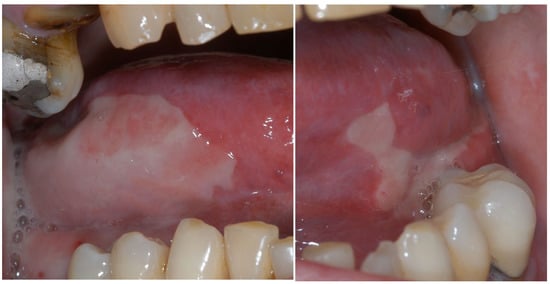

1.1. Oral Mucositis

Prevention and Management of Oral Mucositis